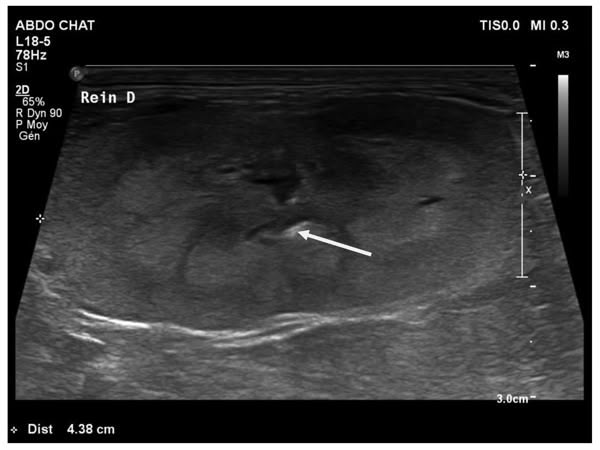

Figure 1

Figure 2